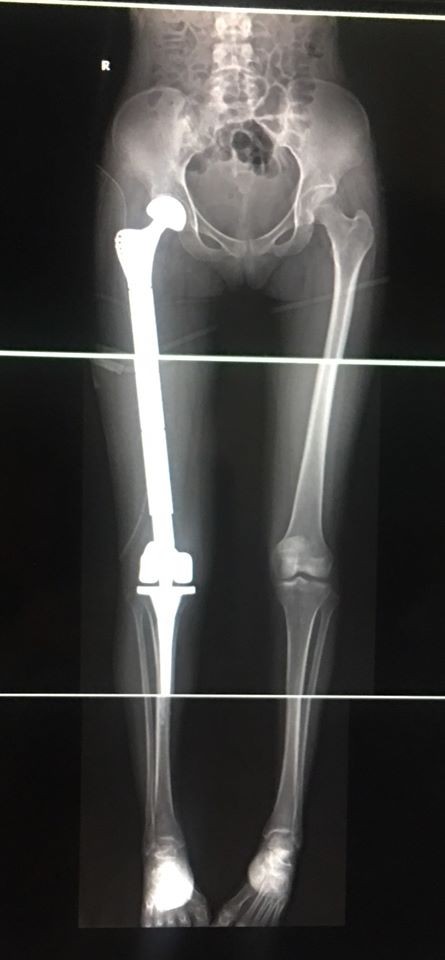

Sau khi thực hiện các xét nghiệm cẩn thận, PGS.TS. Trần Trung Dũng quyết định thực hiện phương án cắt toàn bộ khối xương đùi bị ung thư và thay thế bằng xương đùi Titan cho bệnh nhân.

Ca phẫu thuật diễn ra đầy căng thẳng trong 3 tiếng đồng hồ cuối cùng đã thành công nhờ kinh nghiệm và tay nghề cao của PGS.TS. Trần Trung Dũng. Toàn bộ xương đùi ung thư của cô gái trẻ đã được lấy ra để thay thế bằng xương đùi Titan, đồng thời thay khớp háng và khớp gối toàn phần và khâu phục hồi lại các điểm bám gân cơ.

Phim chụp lại sau mổ của bệnh nhân H. Ảnh: Sơn Tùng

Sau thành công của ca mổ kỳ tích này, PGS.TS. Trần Trung Dũng cho biết: “Ca phẫu thuật đã diễn ra khẩn trương và an toàn, toàn bộ xương ung thư của bệnh nhân H. đã được lấy ra và thay bằng xương đùi Titan. Do mất ít máu trong khi mổ, nên bệnh nhân sẽ sớm hồi phục, giữ được chức năng của chi và có thể vận động bình thường trở lại.”

Chia sẻ về những khó khăn trong quá trình phẫu thuật, PGS.TS. Dũng cho hay: Đây là một ca phẫu thuật lớn và khó. Bởi để đảm bảo chức năng của xương đùi, khớp háng và gối, cần đặt dụng cụ thật chính xác, nếu không sẽ dễ dẫn đến ngắn chi, đồng thời, phải khâu phục hồi lại khối cơ mông và đùi như giải phẫu ban đầu, để tạo độ vững cho khớp háng và gối, tránh trật khớp về sau. Ngoài ra, việc đảm bảo cắt hết khối u, vô khuẩn dụng cụ và kiểm soát lượng máu mất của bệnh nhân vô cùng quan trọng trong phẫu thuật.